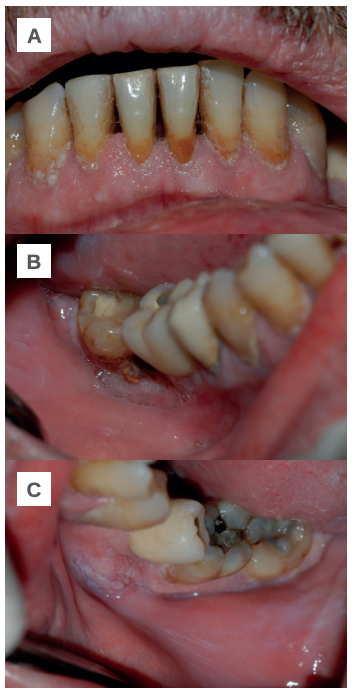

Transcurridos dos meses su dermatólogo sustituye la prednisona por 25 mg de azatioprina cada 24 horas, pero tras tres semanas es necesario interrumpir el tratamiento por fuertes molestias gastrointestinales y una ligera recidiva de las lesiones en la mucosa yugal. Con el fin de volver a estabilizar al paciente, se le prescriben bajas dosis de prednisona (10 mg cada 24 horas) con resultados positivos y una considerable remisión de las lesiones. El paciente se mantiene asintomático y sin recidiva de nuevas lesiones (Figuras 2 A- B y C).